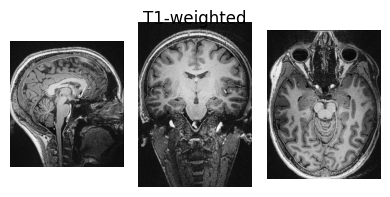

Inspect input data#

Here we define a function we will use to visualise NIfTI images so we can view some of the input data:

show_nii(glob("bids/sub-*/ses-*/anat/*T1w*nii*")[0], title="T1-weighted")